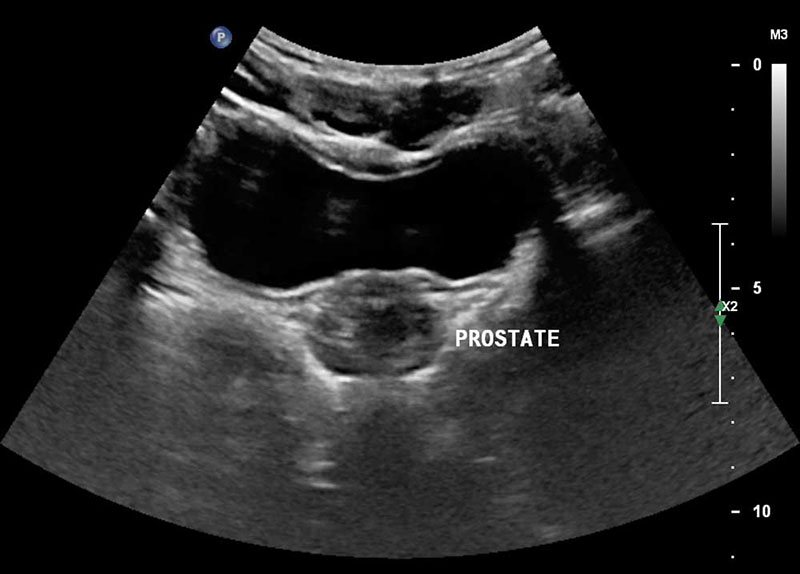

Трансабдоминальное УЗИ представляет собой безболезненный и доступный метод ультразвукового исследования, при котором врач осматривает предстательную железу через брюшную полость. Процедура не требует специальной подготовки и подходит даже тем, кто боится медицинских вмешательств.

Диагностика позволяет оценить размеры и структуру простаты, а также выявить признаки воспаления, аденомы или других патологических изменений. В медицинском центре доктора Бегмы УЗИ проводится на современном оборудовании экспертного класса. Это гарантирует точность выявления патологий даже на начальных стадиях.